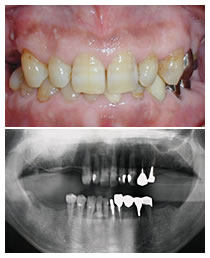

写真の上が、治療前の口腔内写真で、下がレントゲンです。

12本のインプラントを植立し、全額補綴処置をおこないました。臼歯部の咬合高径(咬み合わせの高さ)を上げて安定させました。